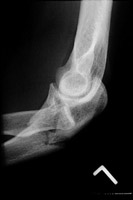

- Click on the image for a larger versionBLateral radiograph of the elbow. This demonstrates posterior dislocation of the radial head, a "reversed" Monteggia injury (Bado type II).

Monteggia fracture-dislocations are classified by the Bado system. Bado type I injuries are characterized by a proximal ulnar fracture with anterior dislocation of the radial head. This is due to a forceful pronation injury of the forearm and is the most common type. Bado type II injuries are "reversed" Monteggia fracture-dislocation injuries. Here, there is posterior angulation of the ulnar fracture site and posterior dislocation of the radial head. Bade type III and IV injuries are rare.